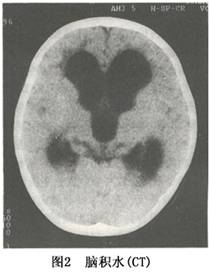

其他輔助檢查:CT或MRI可確定腦室擴大及程度及皮質萎縮的程度,有時可同時了解引起腦積水的原因。此外,CT或MRI還能了解腦積水是急性腦積水還是慢性腦積水,為臨床處理措施的套用提供依據。在腦積水的診斷中,應注意與腦萎縮引起的腦室擴大相區別,後者腦室擴大的同時可明顯地顯示出側裂或腦溝,甚至可有腦溝及腦裂的明顯擴大。另外診斷腦積水應儘可能明確是梗阻性腦積水還是交通性腦積水。

鑑別診斷:低級星形細胞瘤、腦室內囊腫,可通過MRI進行鑑別,也需要與局限性腦室擴大相鑑別。